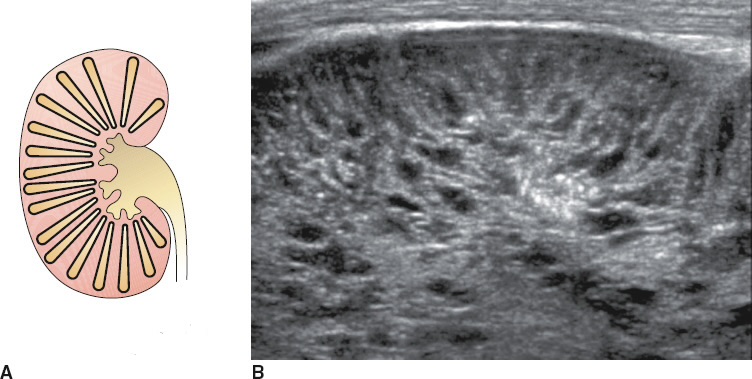

Chronic kidney failure. Small, echogenic. Cortical thinning. Loss of Cortico- medullary differentiation. Renal cysts

Arpkd, autosomal recessive polycystic kidney disease. Dilation of renal collecting tubules